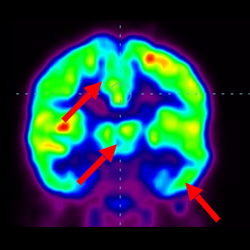

細(xì)胞治療后,藍(lán)色和黑色區(qū)域減少,并且看到更活躍的區(qū)域。這表明損傷減少并改善了大腦功能。

這證明細(xì)胞療法是治療腦癱兒童安全有效的方法。細(xì)胞療法可以更新大腦損傷的核心,并且可以通過 PET CT 掃描來監(jiān)測大腦的改善情況。這些細(xì)胞療法與標(biāo)準(zhǔn)治療一起促進(jìn)腦癱兒童的生長和改善。